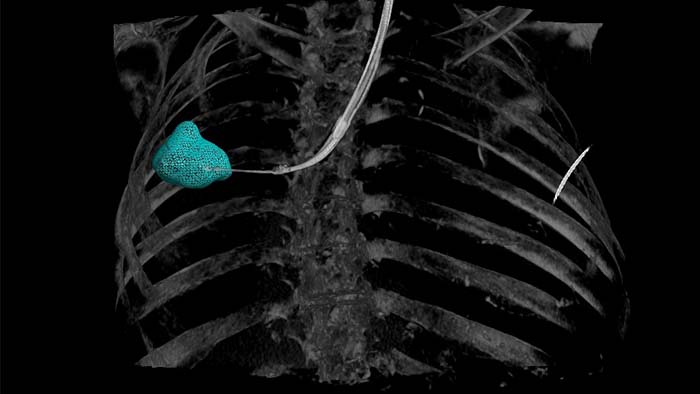

Perform a wide range of routine and complex interventional procedures easily and confidently with the advanced system connectivity and innovative geometry of the Azurion biplane system for neuro interventions with SmartCT1 for 3D applications to speed up confident decision-making.

Image Guided Therapy System Azurion